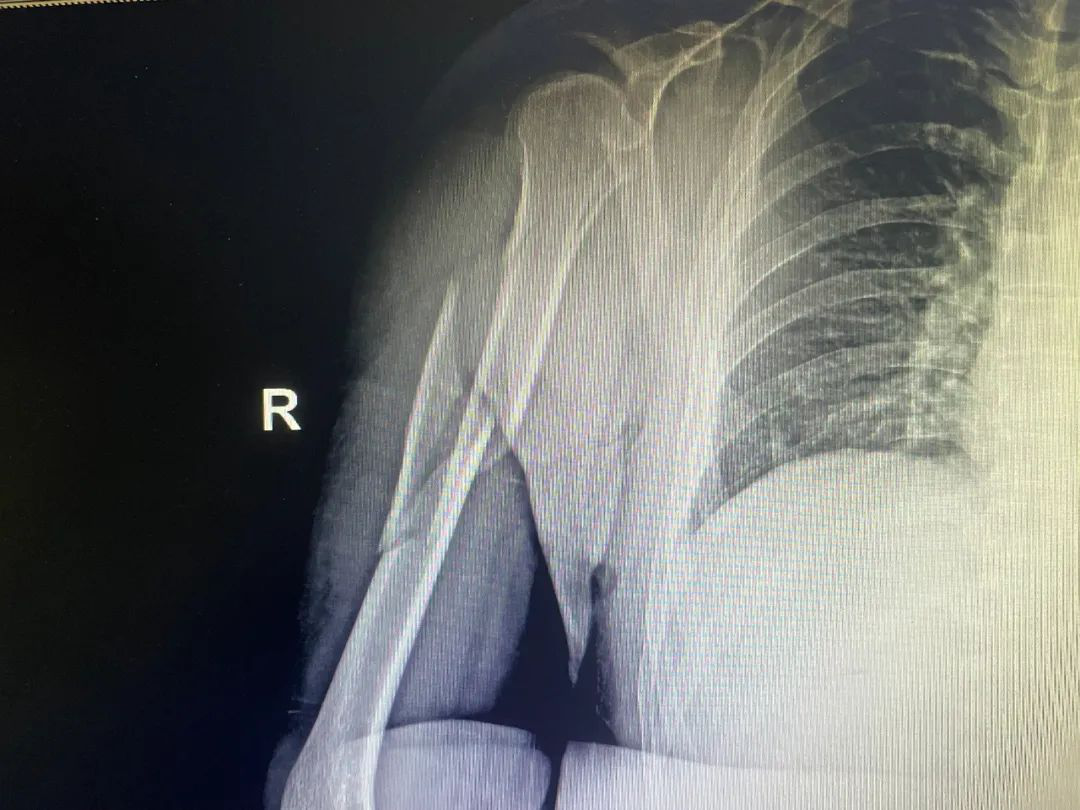

面对年轻人的肱骨干骨折,怎么治疗才好?保守还是手术?内固定还是外固定?

近日,滑雪的火热让肱骨干骨折突然多了起来。面对年轻人的肱骨干骨折,怎么治疗才好?保守还是手术?内固定还是外固定?